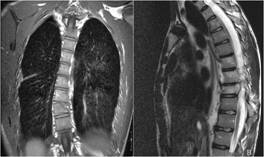

Chylothorax After Thoracic Vertebral Fracture

YA Karamustafaoglu, MD, R Mammedov MD, G Reyhan MD, F Yank MD, Y Yoruk, MD,